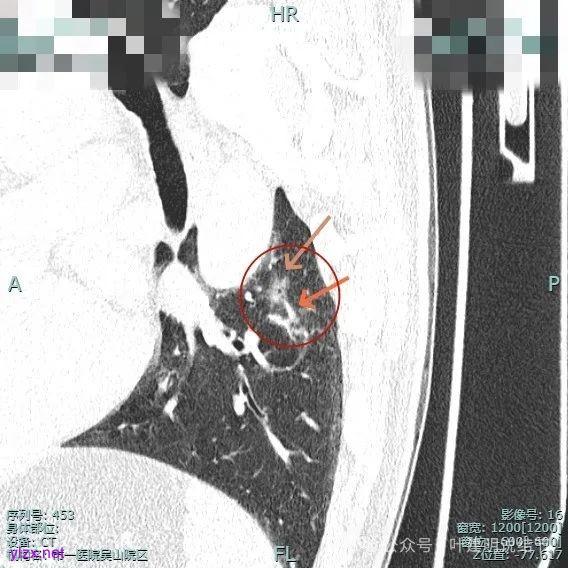

主病灶位于下叶后基底段下肺静脉水平,次病灶在同一层面位靠外基底段交界附近。

2、手术问题:由于主病灶不纯,血管进入与增粗明显,随访是有风险的,应该考虑手术切除。而若主病灶要切除,那么次病灶离它这么近,应该也要考虑一并切除,不然一是只切主病灶后若次病灶刚好位于切缘处,以后观察有无进展困难,二是以后若仍考虑手术,增加难度。从连续层面看以,主病灶位于后基底段靠近背段处,单纯后基底段切除切缘可能不太够;次病灶则靠近外基底段,如果单纯切除后基底段也不安全。经过科室讨论,意见是可以考虑背段加后基底段切除,后基底段与外基底段之间还要往外基底段侧多切过去点。或者后基底段切除,但离断段间平面时向背段侧扩大切除一部分,往外基底段侧也扩大切除一部分。如果切除基底段,还要往背段切过去点,那下叶余下也不多了。手术方式比较纠结。

上图蓝色箭头所指的是医用定位胶,天蓝色箭头是次病灶,红色箭头是主病灶,设计的切除线如虚线所示。我们打算进胸后确定定位胶所在平面,因为包括两处病灶均在同一平面上,然后我们游离下肺韧带,将后基底段此部分肺组织向下解剖游离开,直到下肺静脉下缘,并贴着下叶静脉边缘往肺实质深面用切割缝合器切开并闭合肺切缘,按CT上大概距离推算,到越过次病灶深度后转向胸肋面,切除该范围内的肺组织。